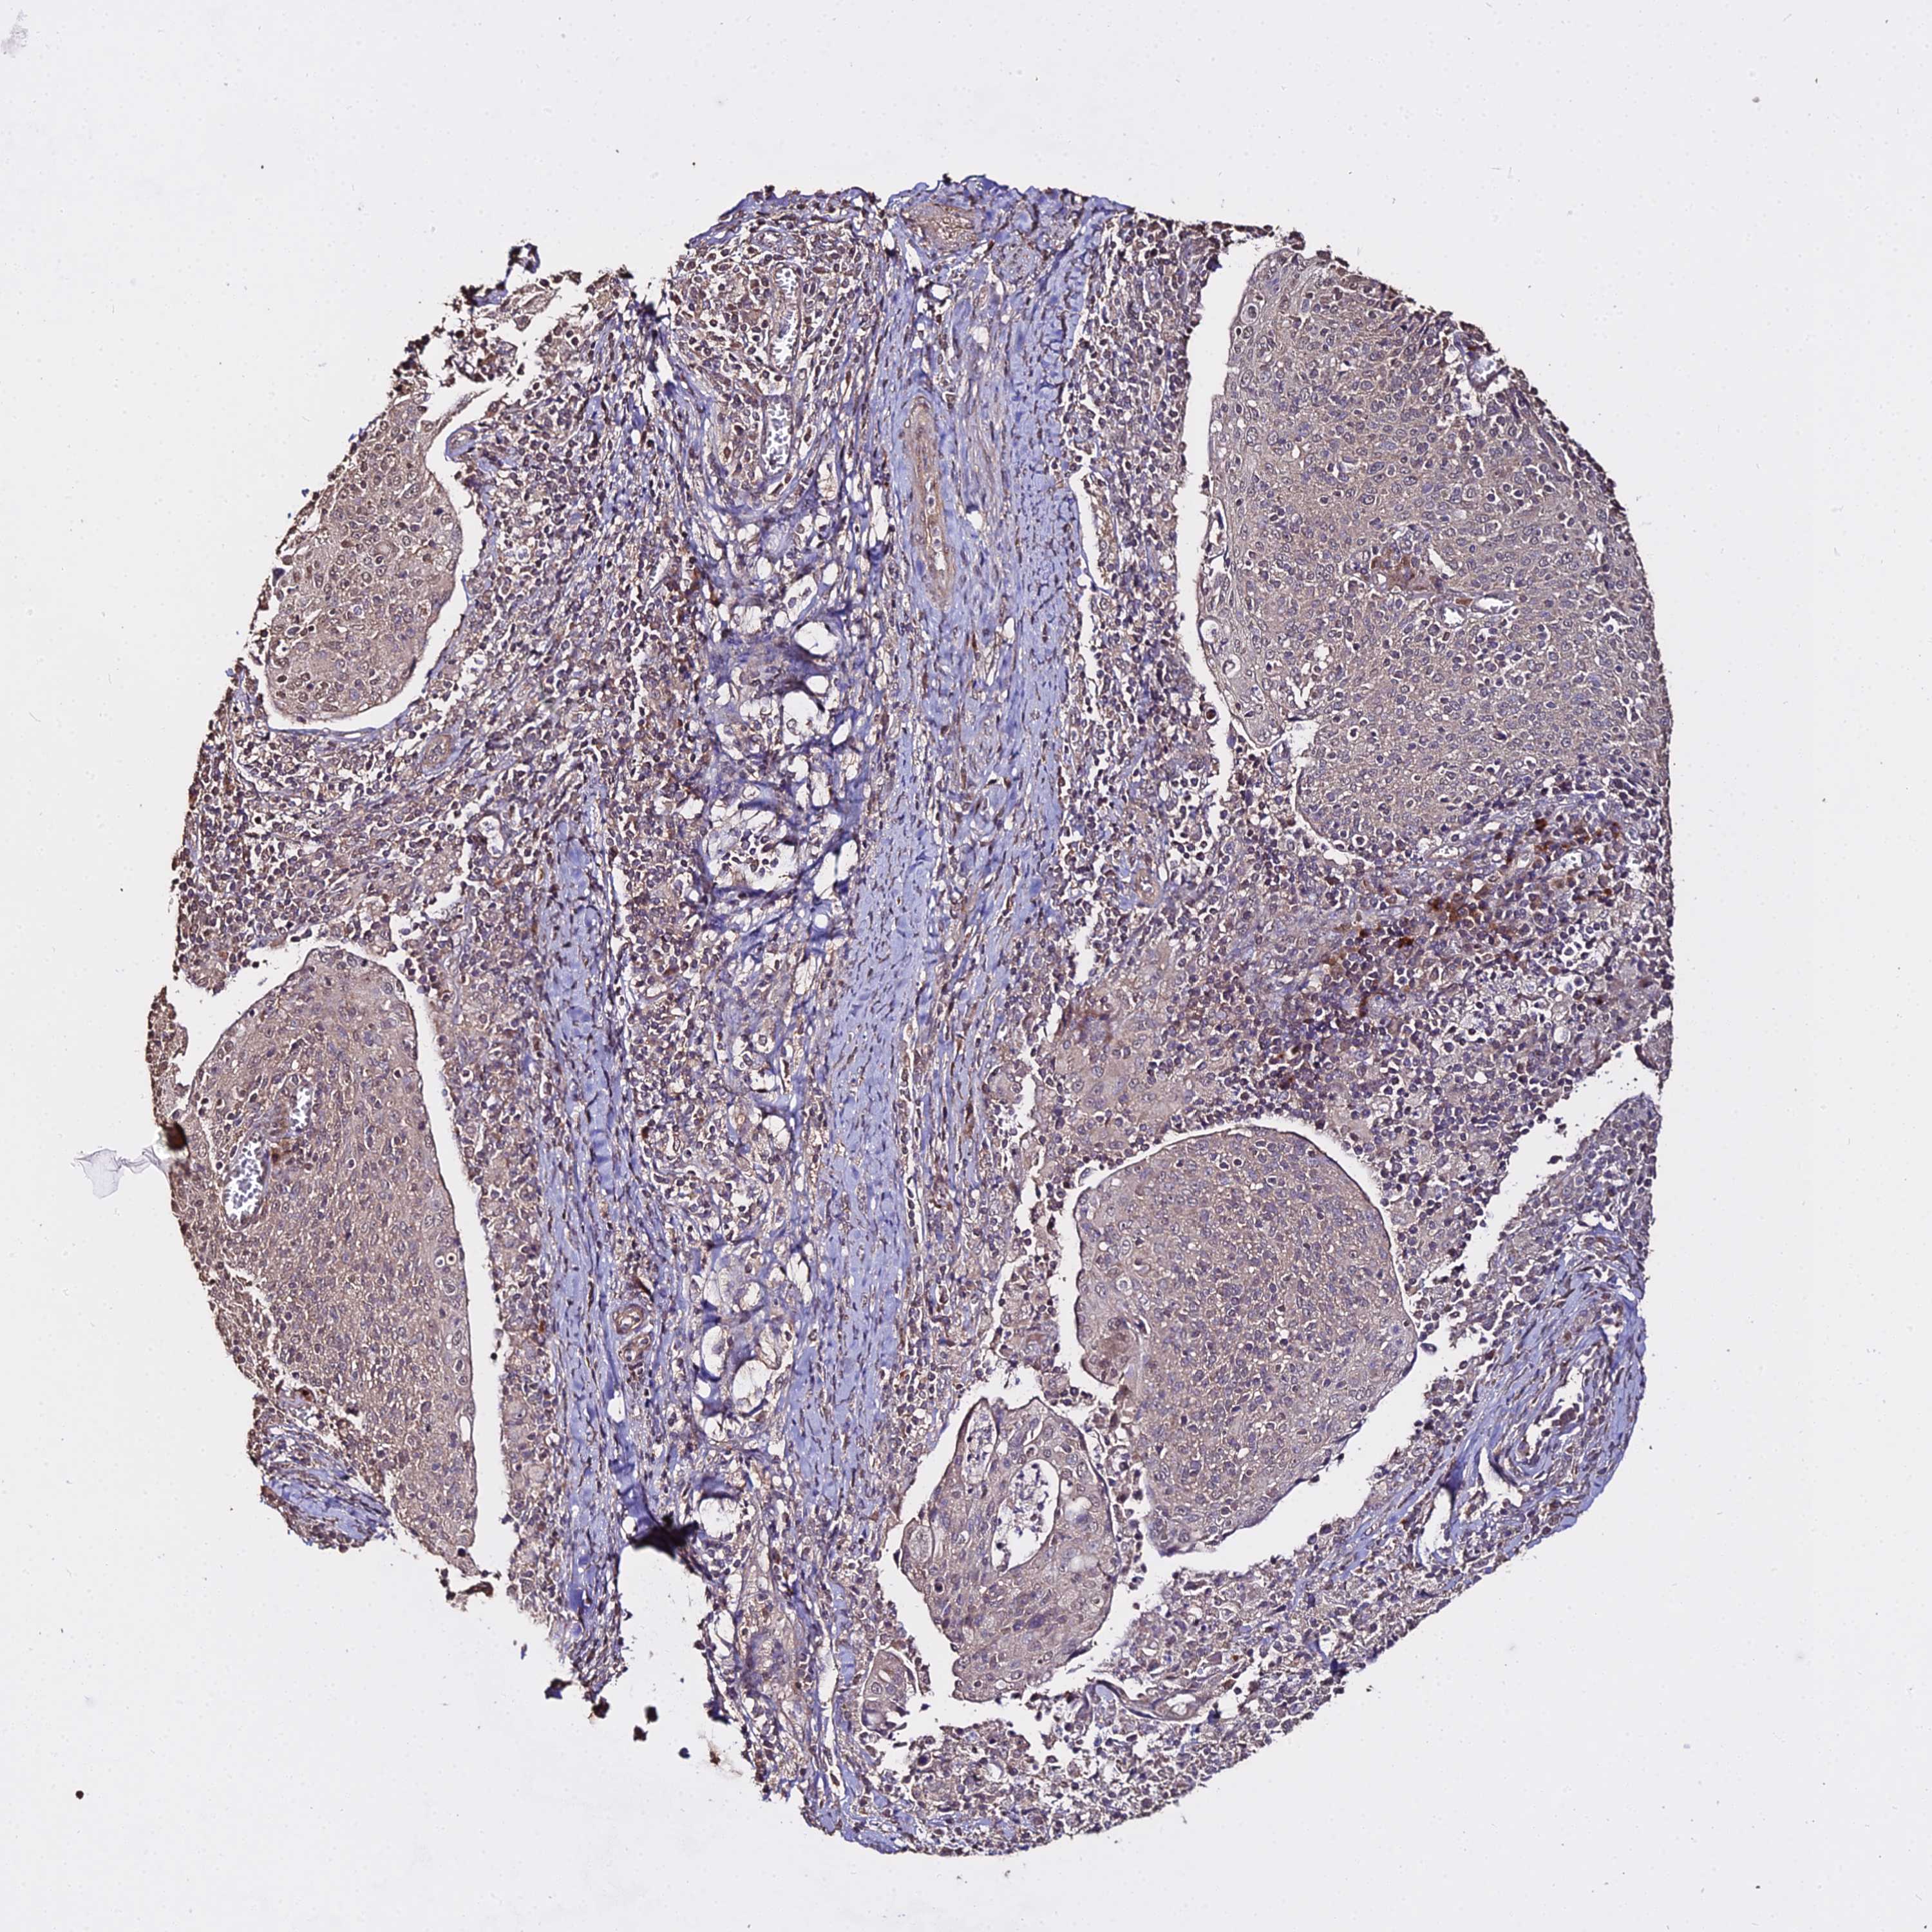

CERVICAL CANCER - Protein expressioni

A mouse-over function shows sample information and annotation data. Click on an image to view it in a full screen mode. Samples can be filtered based on level of antibody staining by selecting one or several of the following categories: high, medium, low and not detected. The assay and annotation is described here.

Note that samples used for immunohistochemistry by the Human Protein Atlas do not correspond to samples in the TCGA dataset.

Antibody stainingi

Antibody staining in the annotated cell types in the current human tissue is reported as not detected, low, medium, or high, based on conventional immunohistochemistry profiling in selected tissues. This score is based on the combination of the staining intensity and fraction of stained cells.

Each image is clickable and will lead to virtual microscopy that enables deeper exploration of all samples and also displays staining intensity scores, fraction scores and subcellular localization as well as patient and tissue information for each sample.

Antibody HPA044498

Antibody HPA053705

Squamous cell carcinoma, NOS

Adenocarcinoma, NOS